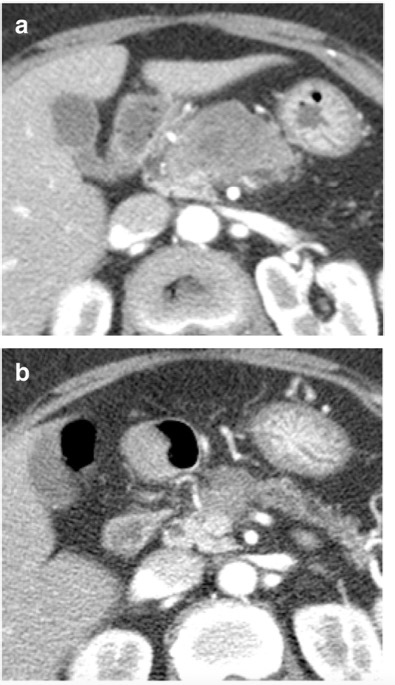

图 70岁女性,因胰腺癌接受新辅助治疗。(a)在诊断时和(b)新辅助治疗后的增强CT图像。所有六位阅读者对再分期CT的肿瘤可切除性评估为 "边缘-可切除"。五位阅读者评估肿瘤反应等级为1(反应良好)。由于肿瘤周围的纤维化和粘连,进行了门静脉/肠系膜上静脉切除和端对端吻合术,但病理检查没有静脉侵犯的证据。切缘为阴性,YpT2N0分期。